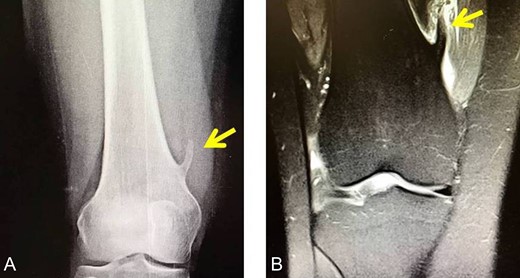

The second case involved an 18 years old male with pain and swelling at the anterior surface of the left knee, under the rectus femoris muscle over the patella. Symptoms exacerbated during knee bending over 90 degrees. X-rays and MRI revealed an extra-articular exostosis, just over the suprapatellar pouch (Figs. 3A and B). Under general anesthesia, a standard antero-lateral portal was used to access the knee arthroscopically. The capsule of the suprapatellar pouch was divided providing access to the adjacent extra-articular osteochondroma. Through a medial, a far supero-medial and supero-lateral portal, the exostosis resected by using an osteotome and removed with a grasper through the supero-lateral portal. The lesion had maximum dimensions 3.1 × 1.4 cm and its histopathological examination set the diagnosis of osteochondroma. Postoperatively, the patient was pain free with full range of knee motion. No recurrence was observed at 9 months (Fig. 4).

(A) X-ray of the exostosis in the second patient, (B) MRI depicts the lesion.